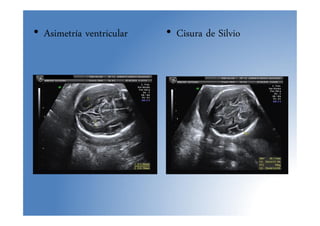

• Asimetría ventricular • Cisura de Silvio

• Asimetría ventricular• Cisura de Silvio